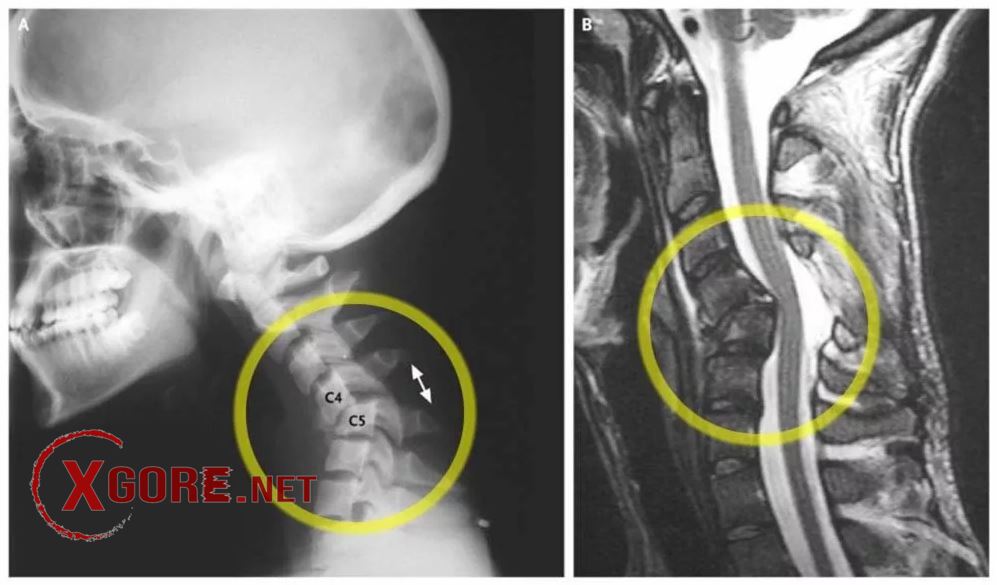

There is no information about the victim. His neck was almost severed in the accident.